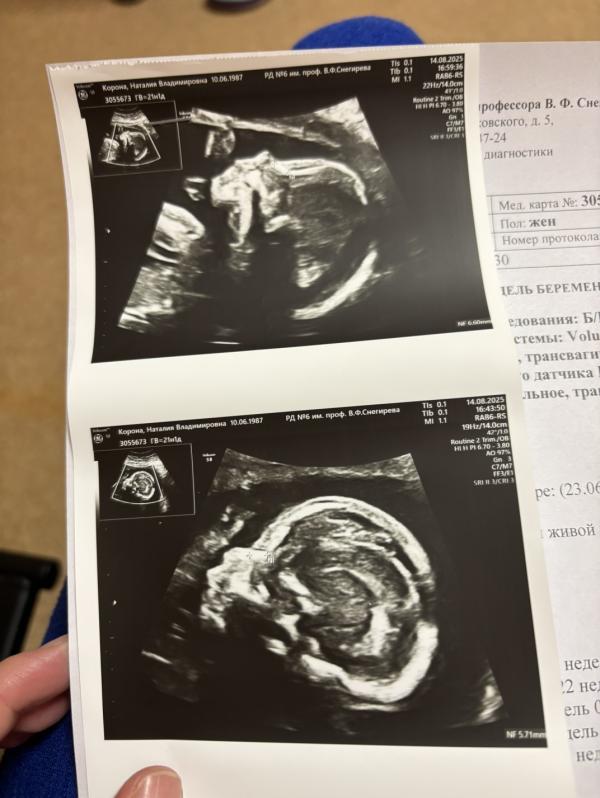

На 2-м узи четко и ясно видно мальчика 💙

На узи он смешной такой, не давал сосчитать пальчики на ручках, потому что ловил ручками свою ножку ))) нашел себе развлечение.